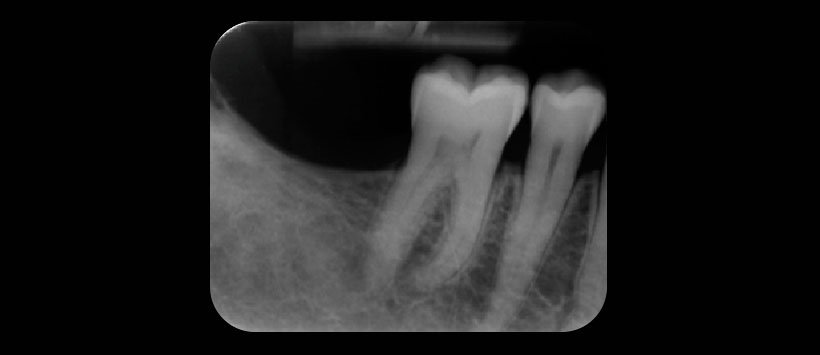

Figura 1: Radiografìa panorámica que muestra múltiples imágenes radiopacas a nivel periapical de la región anteroinferior y molar posteriore. Corte transaxial a nivel distal de la pieza 47. Muestra una imagen heterogenea, signos radiográficos sugerentes de displasia cemento-ósea florida. Imágenes correspondientes a una paciente femenino de 49 años de edad cuyo motivo de consulta es el dolor mandibular en la region mandibular derecha.